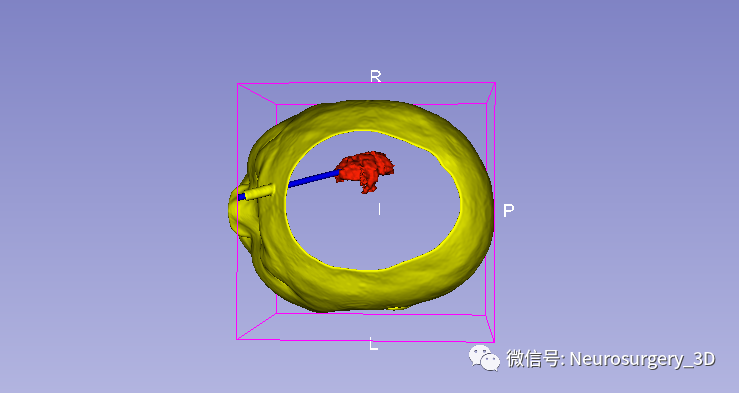

1、利用Ruler测量出穿刺血肿靶点至穿刺外口的距离,并设计出穿刺路径顺血肿长轴走形在血肿中心(并非如下图所示所有穿刺路径均与矢状面平行、请注意穿刺深度),避开颅内重要结构如额窦、上矢状窦等。

入颅点避开了额窦、上矢状窦

透视化血肿状态下显示穿刺路径走形在血肿中心